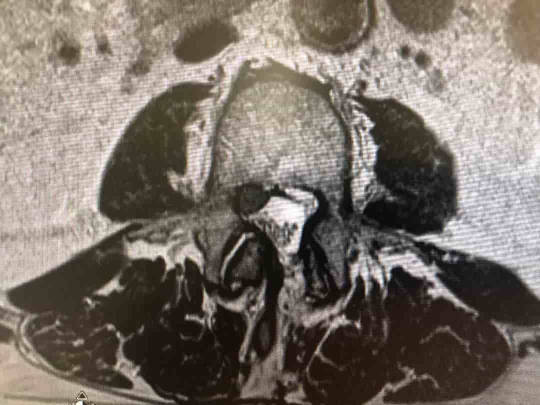

Cuando se produce una hernia discal muchas veces aparece una lumbociática. Una vez que has acudido a un médico especialista y tras una correcta exploración, tenemos un diagnóstico de sospecha que confirmaremos mediante una resonancia magnética (RM). La RM es la principal prueba de imagen que tenemos para poder diagnosticar una hernia discal. En las ocasiones en las que no se pueda realizar una RM (personas con marcapasos), la prueba que escogeremos es un escáner, que aunque no tienen la misma calidad de imagen si puede ayudarnos a diagnosticar una hernia discal. Sin embargo es muy importante poner en relación los síntomas que tenemos con las imágenes de resonancia, de este modo evitaremos achacar síntomas a lesiones que realmente no las están produciendo.